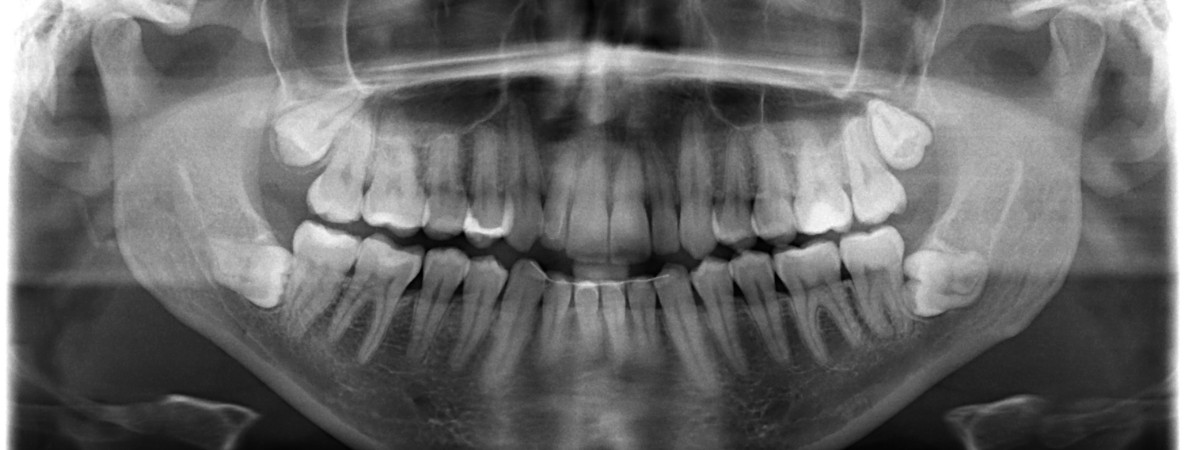

Panoramica dentale – ortopantomografia

Panoramica dentale è una ortopantomografia delle arcate dentarie che consente una visione dettagliata dello stato di tutti i denti, del tessuto gengivale e dell’osso mascellare. Viene utilizzata sia a scopo diagnostico sia preventivo, poiché permette di individuare problemi non visibili a occhio nudo.

Cos’è l’ortopantomografia?

L’ortopantomografia è indispensabile quando vogliamo avere una visione completa di tutti i denti e delle strutture ossee circostanti. Viene eseguita come radiografia orientativa alla prima visita, ma è consigliata anche durante il controllo annuale.

Viene eseguita in tutti i casi in cui è più importante avere una panoramica dell’intera dentatura piuttosto che i dettagli di un singolo dente.

Oltre alla funzione orientativa, è impiegata nella pianificazione delle terapie protesiche, ma anche in ortodonzia e in chirurgia orale, per la progettazione di impianti o l’estrazione di denti inclusi.

L’ortopantomografia digitale è la tipologia più comune di immagine dentale e mascellare. È neccessario sottolinerae che la dose di radiazioni emessa è notevolmente ridotta, mentre la precisione diagnostica è superiore rispetto agli ortopantomografi tradizionali.

L’ortopantomografia o ortopanoramica è un’immagine bidimensionale che rappresenta in un’unica proiezione mascelle, denti, articolazioni e strutture circostanti. Viene utilizzata soprattutto come primo passo nella diagnosi, perché è rapida, semplice e comporta un’esposizione a radiazioni molto bassa. Fornisce una panoramica dello stato generale: permette di individuare carie in zone difficili da raggiungere, valutare lo stato dell’osso, la posizione dei denti del giudizio, eventuali alterazioni a livello delle radici, cisti o altre lesioni più estese.